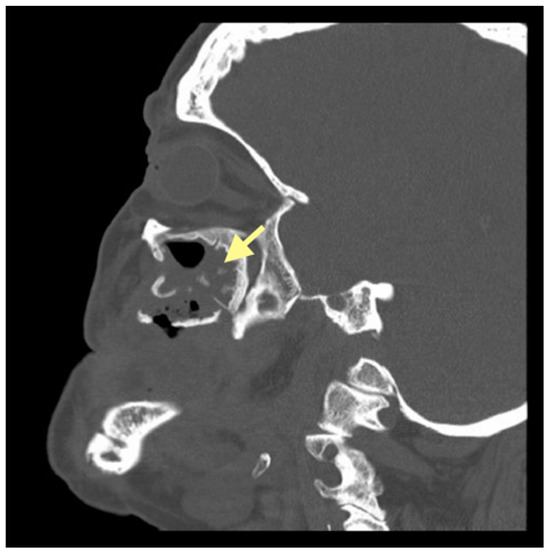

2.3. The Third Case (See Table 1)

The third patient was a 75-year-old female with osteonecrosis of the mandible and maxilla in the fourth and in the second quadrant (see Figure 7, Figure 8 and Figure 9). The patient had third-stage jaw osteonecrosis. In 2023, the patient was diagnosed with osteonecrosis of the upper and lower jaw caused by antiresorptive therapy (until August 2021, the patient regularly used Zolendronic acid; then, this drug was replaced by the RANKL inhibitor Denosumab). The treatment was periodically complicated by submandibular and submental abscesses. In addition, due to the progression of the underlying disease, constant courses in chemotherapy were administered. The patient underwent three operations, which included sequestrectomy of the jaw with simultaneous use of A-PRF, antrotomy with revision of the maxillary sinus, closure of the oroantral communication, and opening and revision of abscesses of the soft tissues (see Figure 10 and Figure 11)

Figure 8.

CT of the head and facial bones (16 December 2024).